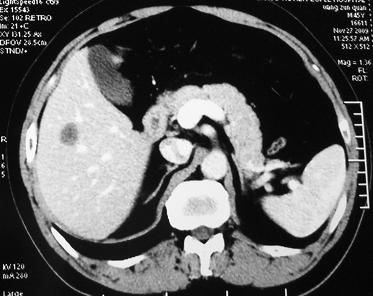

男 45岁。体检b超发现肝脏一低密度病变,怀疑是血管瘤,来ct检查。

ct平扫:在肝右后下叶一直径约2厘米的圆形低密度病变,ct值约32hu。

增强三期都未强化。后经mri检查,t1wi及t2wi为等信号,与肝脏等信号。